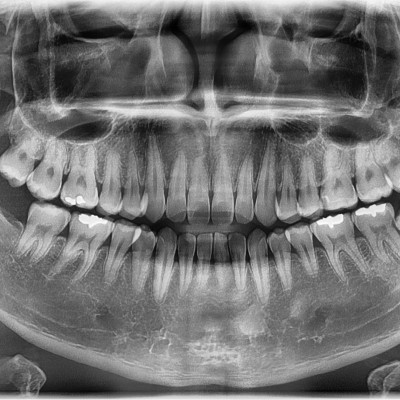

#48 사랑니 발치 N새글 #48 사랑니 발치 구강 외과 전문의가 당일 발치했습니다. -----------------------------..